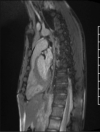

The Society for Cardiovascular Magnetic Resonance (SCMR) is an international society focused on the research, education, and clinical application of cardiovascular magnetic resonance (CMR). Case of the week is a case series hosted on the SCMR website ( https://www.scmr.org ) that demonstrates the utility and importance of CMR in the clinical diagnosis and management of cardiovascular disease. Each case consists of the clinical presentation and a discussion of the condition and the role of CMR in diagnosis and guiding clinical management. The cases are all instructive and helpful in the approach to patient management. We present a digital archive of the 2020 Case of the Week series of 11 cases as a means of further enhancing the education of those interested in CMR and as a means of more readily identifying these cases using a PubMed or similar search engine.